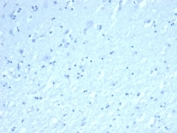

Negative control: IHC testing of FFPE human brain tissue with INHA antibody (clone INHA/8872R) at 2ug/ml. HIER: boil tissue sections in pH 9 10mM Tris with 1mM EDTA for 20 min and allow to cool before testing.